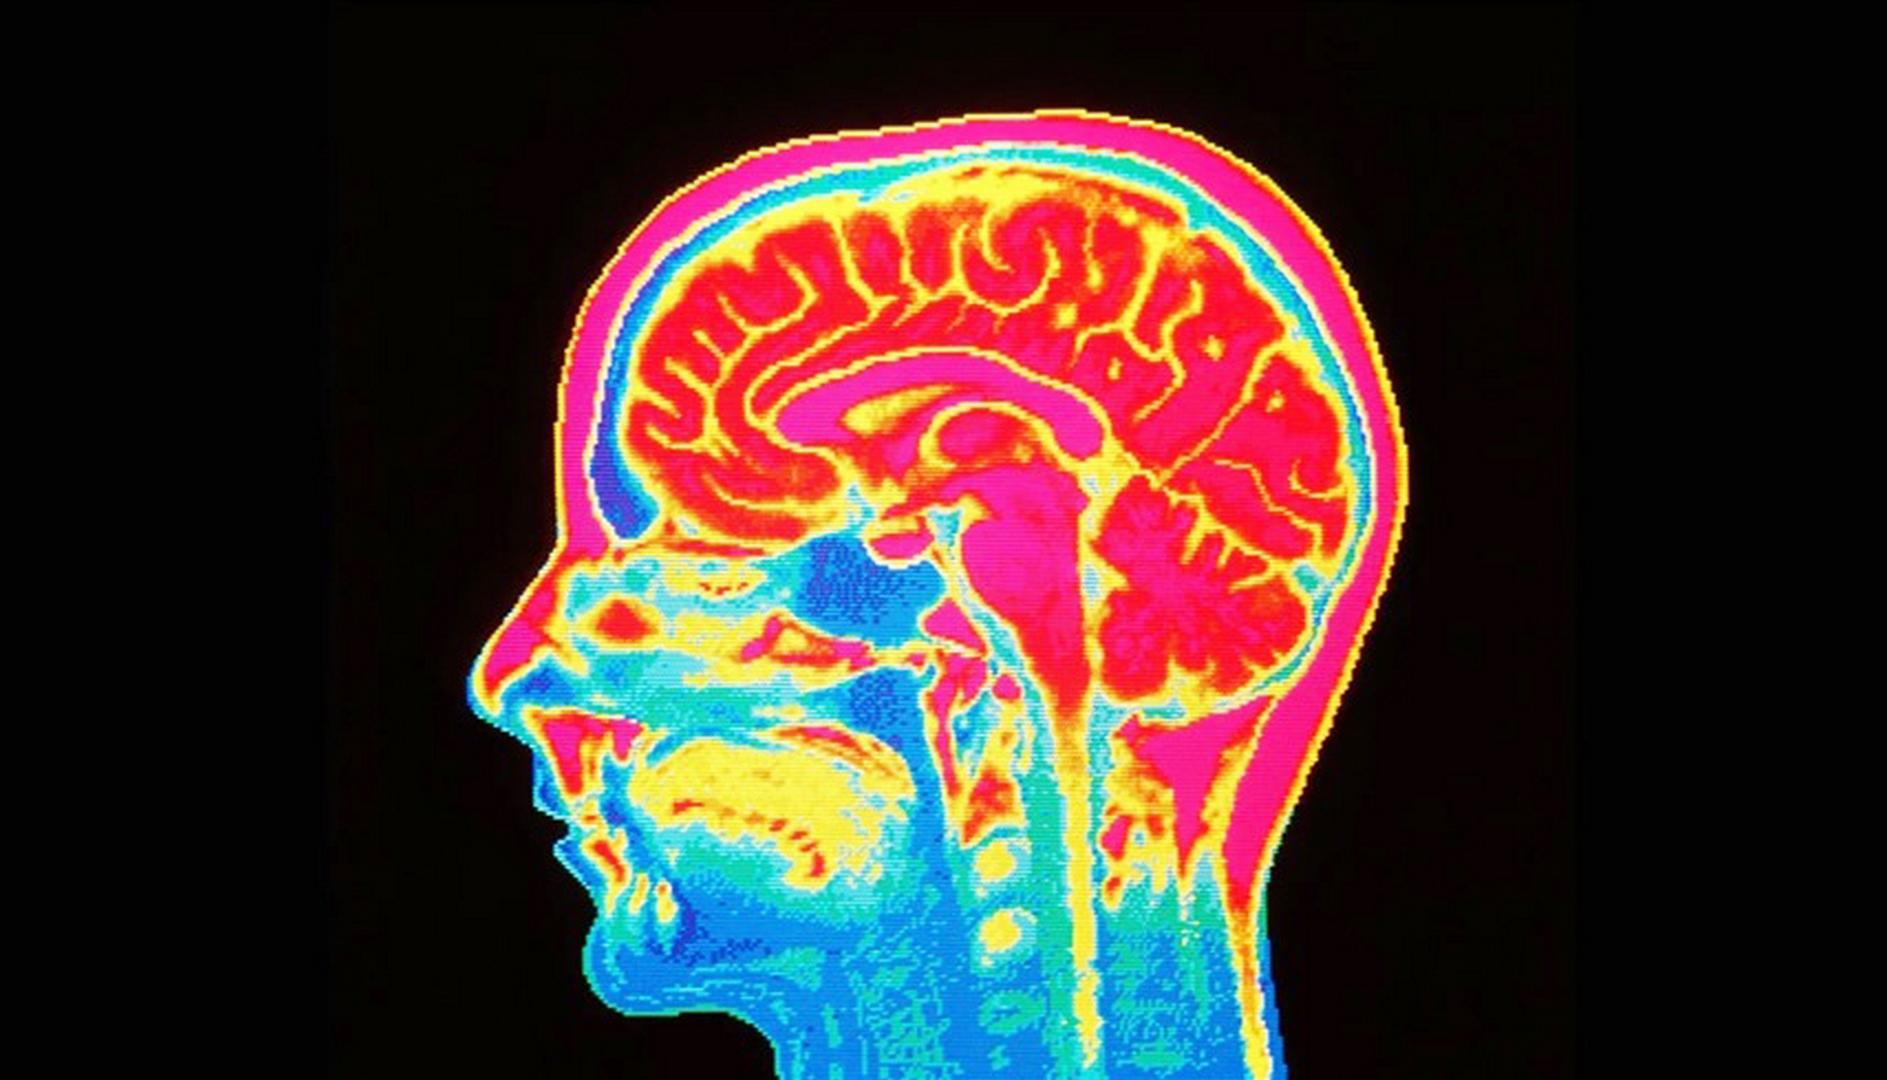

أشارت دراسة جديدة إلى أن هناك بعض الأخبار الجيدة في مجال الخرف، فقد وجدت أن أدمغة الناس أصبحت أكبر حجماً على مدى المائة عام الماضية، وهذا الاحتياطي المتزايد للدماغ يمكن أن يقلل من خطر الإصابة بالخرف المرتبط بالعمر.

ووفق “مديكال نيوز توداي”، أفادت الدراسة التي أجريت في جامعة كالفورنيا بأن الأشخاص الذين ولدوا في سبعينيات القرن العشرين كان لديهم أدمغة أكبر بنسبة 6.6% في المتوسط مقارنة بأدمغة الذين ولدوا في الثلاثينيات.

وأشارت إلى أن حجم الدماغ الأكبر يعني زيادة احتياطي الدماغ، ما قد يقلل من خطر الإصابة بالخرف المرتبط بالعمر.

ومن بين البيانات أجرى 3226 شخصاً فحصين بالرنين المغناطيسي كانا مناسبين لهذه الدراسة، 53% منهم نساء، وقاست عمليات المسح الحجم داخل الجمجمة، والمادة الرمادية القشرية، والمادة البيضاء الدماغية، وحجم الحصين، ومساحة السطح القشري، ومقاييس السماكة القشرية.

كما أظهر التحليل أن مواليد 1970 كان حجم المادة البيضاء لديهم أكثر بنسبة 7.7%، والمادة الرمادية القشرية أكبر بنسبة 2.2%، وحجم الحصين أكبر بنسبة 5.7%، ومساحة السطح القشري أكبر بنسبة 14.9%.

وكان المقياس الوحيد الذي انخفض هو السماكة القشرية، الذي كان أقل بنسبة 20.9%.